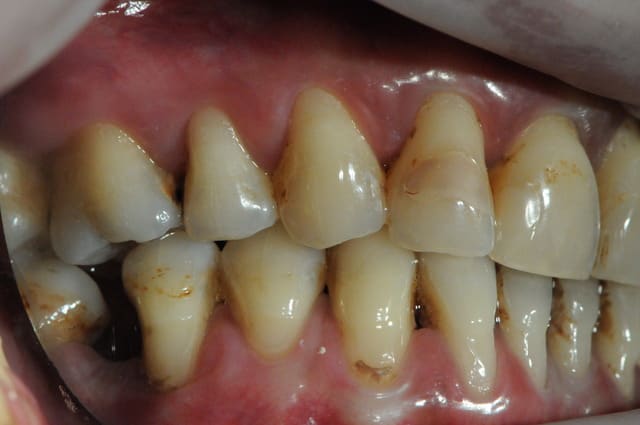

Jeune femme de 35 ans !

pas trop mal foutu au demeurant ( je sais, ça n'a rien à voir) et fumeuse de surcroit .

Ne découvre pas quand elle sourit.

Elle est venue consulter il y a 2 semaines en urgence pour mobilité et état infectieux sur 12.

La 12 est totalement perdue avec sa mobilité 3 sur l'échelle de Mhulmann, ce qui m'ennuie dans ce cas , c'est que le reste des dents, bien qu'étant fortement attaqué par la parodontite, ne soit que très faiblement mobile.